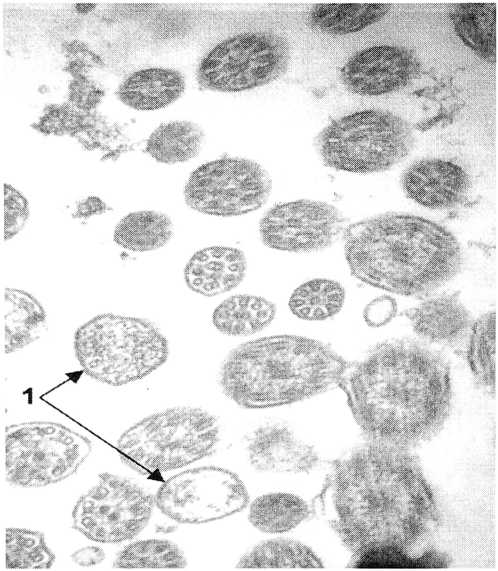

Рис. 9. Гидросальпинкс.

Поперечные срезы ресничек, многие из которых имеют повреждение окружающей их плазмолеммы (1), приводящее к адгезии ресничек между собой. Электронограмма, увеличение ×70000